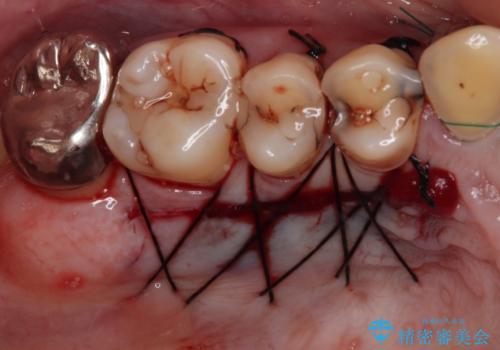

まずは歯肉移植術により顕著に露出している歯根面を被覆して自然な歯肉ラインとし、同時に歯肉の厚みを増大させることで将来の歯肉退縮を予防することを提案しました。

犬歯を中心に、露出量の多かった歯は十分に被覆することができました。

また、歯根のシルエットが見えた術前の状態と比較して、術後は歯肉が非常に厚くなっている状態となりました。

- 外科手術のため、術後に出血、痛みや腫れ、違和感を伴います